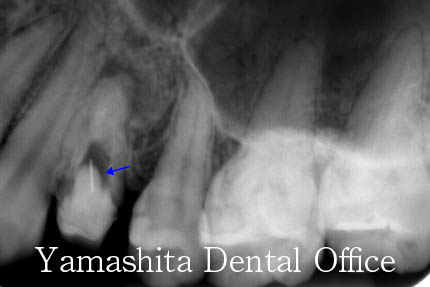

根の先に膿がたまっているのですが、折れたKファイルと呼ばれる器具が邪魔になって、根の管のお掃除が出来ません。

マイクロスコープと超音波器具で折れたKファイルを取り除きました。

根管充填し、根管治療を終わりました。病巣も縮小傾向です。